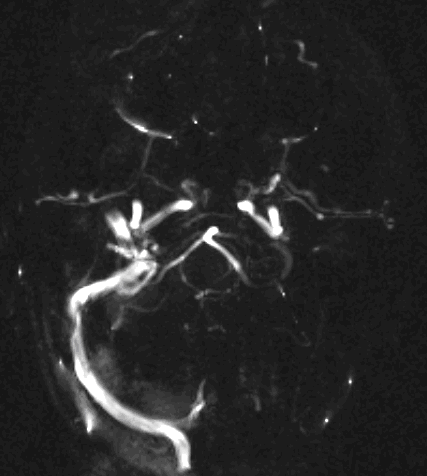

MR angiography (MRA) is an excellent method to visualize brain vessels (arteries, veins, sinuses).

MRA and CTA have completely replaced diagnostic angiography. (Both the sensitivity and the specificity of MRA is greater than 90% in the diagnostics of lesions in the carotid bifurcation.)

CT angiography examination is usually advisory in order to confirm the site of the bleeding. It is also effective when a hemorrhagic tumor is in the differentials, although complete differentiation might only be achieved by follow-up examinations. CTA is also essential in the diagnostics of multiple aneurysms (which are prevalent in 20-30% of the cases based on autopsy reports.) In case of a subarachnoid hemorrhage the consequently developing hydrocephalus and its degree might only be detected on follow-up CT examinations. It is very important to note that an initial brain aneurysm rupture might be followed by a second one within the first 7 – 10 days and the resulting vasospasm carries a much higher risk of mortality than the one at the time of the first SAH. This is why the scrutonius review of the acute diagnostic imaging is essential and it plays a fundamental role in patient treatment. Open brain surgery of the aneurysm (clipping) has been replaced by catheter angiography (DSA) nowadays. The aneurysm is either filled up with thrombogenic coils through its neck or recently bypassing stents are inserted to exclude the aneurysm from the cerebral circulation.